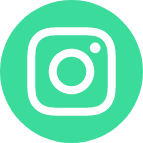

آکوستیک نوروما یا تومور عصب شنوایی، یک تومور خوشخیم است که معمولاً در عصب شنوایی ایجاد میشود. این عصب سیگنالهای صوتی را از گوش داخلی به مغز منتقل میکند. با رشد تومور، فشار روی عصب شنوایی و اعصاب اطراف افزایش یافته و باعث بروز علائمی مانند کاهش شنوایی، وزوز...